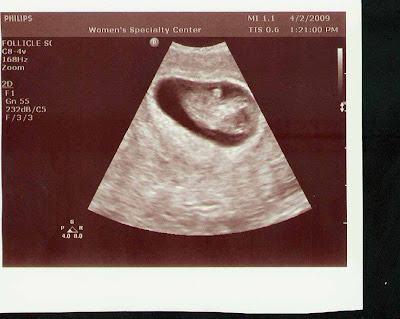

I had a doctor's appointment on Tuesday the 14th with Dr. Isaacs at 10w6d. He released me and told me everything looked GREAT!! Here are the pictures!!! The baby was moving around and cutting flips and waving at us!!

Then yesterday I had a little scare. I started spotting just a tiny little bit about 9 am. I called my OB and luckily they were in the office. I told the nurse that I had a yeast infection and I thought that was all it was but she told m to come right then to the doctor. I got there and had a very detailed ultrasound. We saw the placenta and my cervix and the baby's bladder - everything!!! My OB came in for the ultrasound and immediately said everything looked good - there was no free fluid in my uterus and if I am miscarrying that blood will fill my uterus or stomach before I start seeing it on the outside. He said it was probably caused by the yeast infection and all of the meds that I am taking. I am to take it easy all weekend and come back Tuesday for my regular OB appointment. The baby was 11w2d but measured 11w3d!!! Last night we started rearranging the furinture that I already have in the nursery and cleaning that room (it has mostly been used for storage) annd mvoing some furniture from other places in the house in there. My spare bedroom furniture matches what I am buying for the nursery and I didn't need all of that in the spare room so I swiped some of it last night.